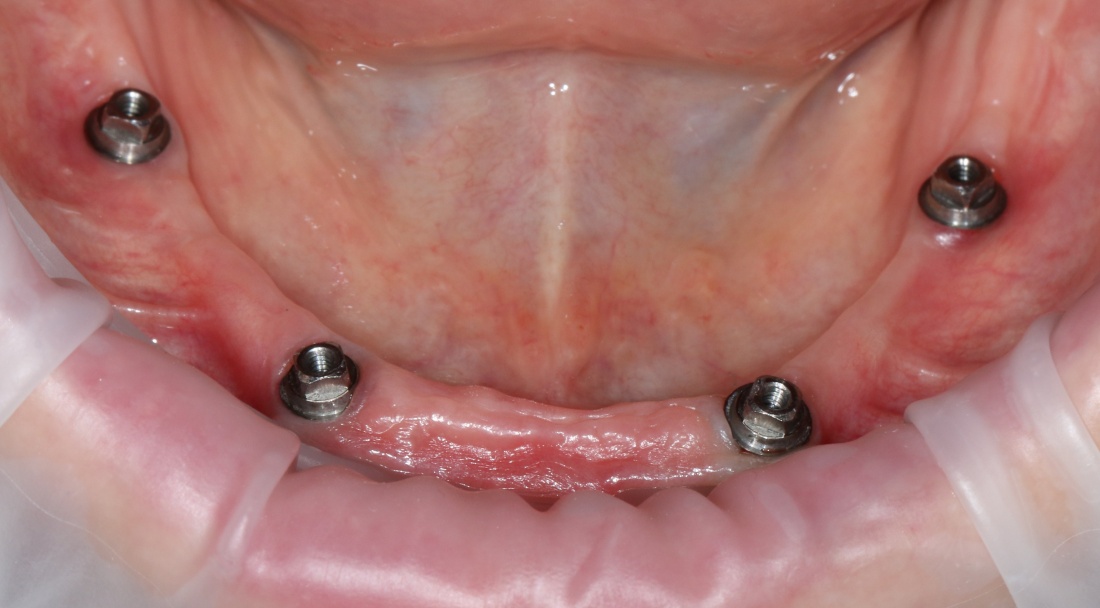

Рекомендации по установке имплантов. Для всех. Часть V.